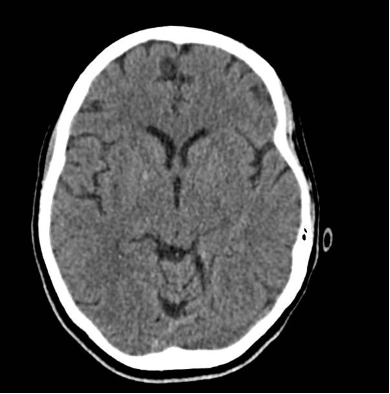

The patient’s imaging diagnostics were significant for a head CT that showed high-density foci in the globi pallidi, right greater than left, likely reflecting calcification (Figure 1) and a brain MRI completed on initial admission in late March that was significant for grossly abnormal subcortical enhancement with associated T2/Flair hyperintensity noted in the bilateral medial thalami, posterior putamen, midbrain, substantia nigra, and periaqueductal gray matter (Figure 2). On initial admission, clinicians performed an EKG, which was significant for diffuse T-wave inversions in the inferior and precordial leads (e.g. cerebral T-waves) that resolved on repeat testing (Figure 3).

Figure 1. CT Head completed on day of initial admission. Findings significant for high density foci in the right global palladi that likely reflects calcification/mineralization